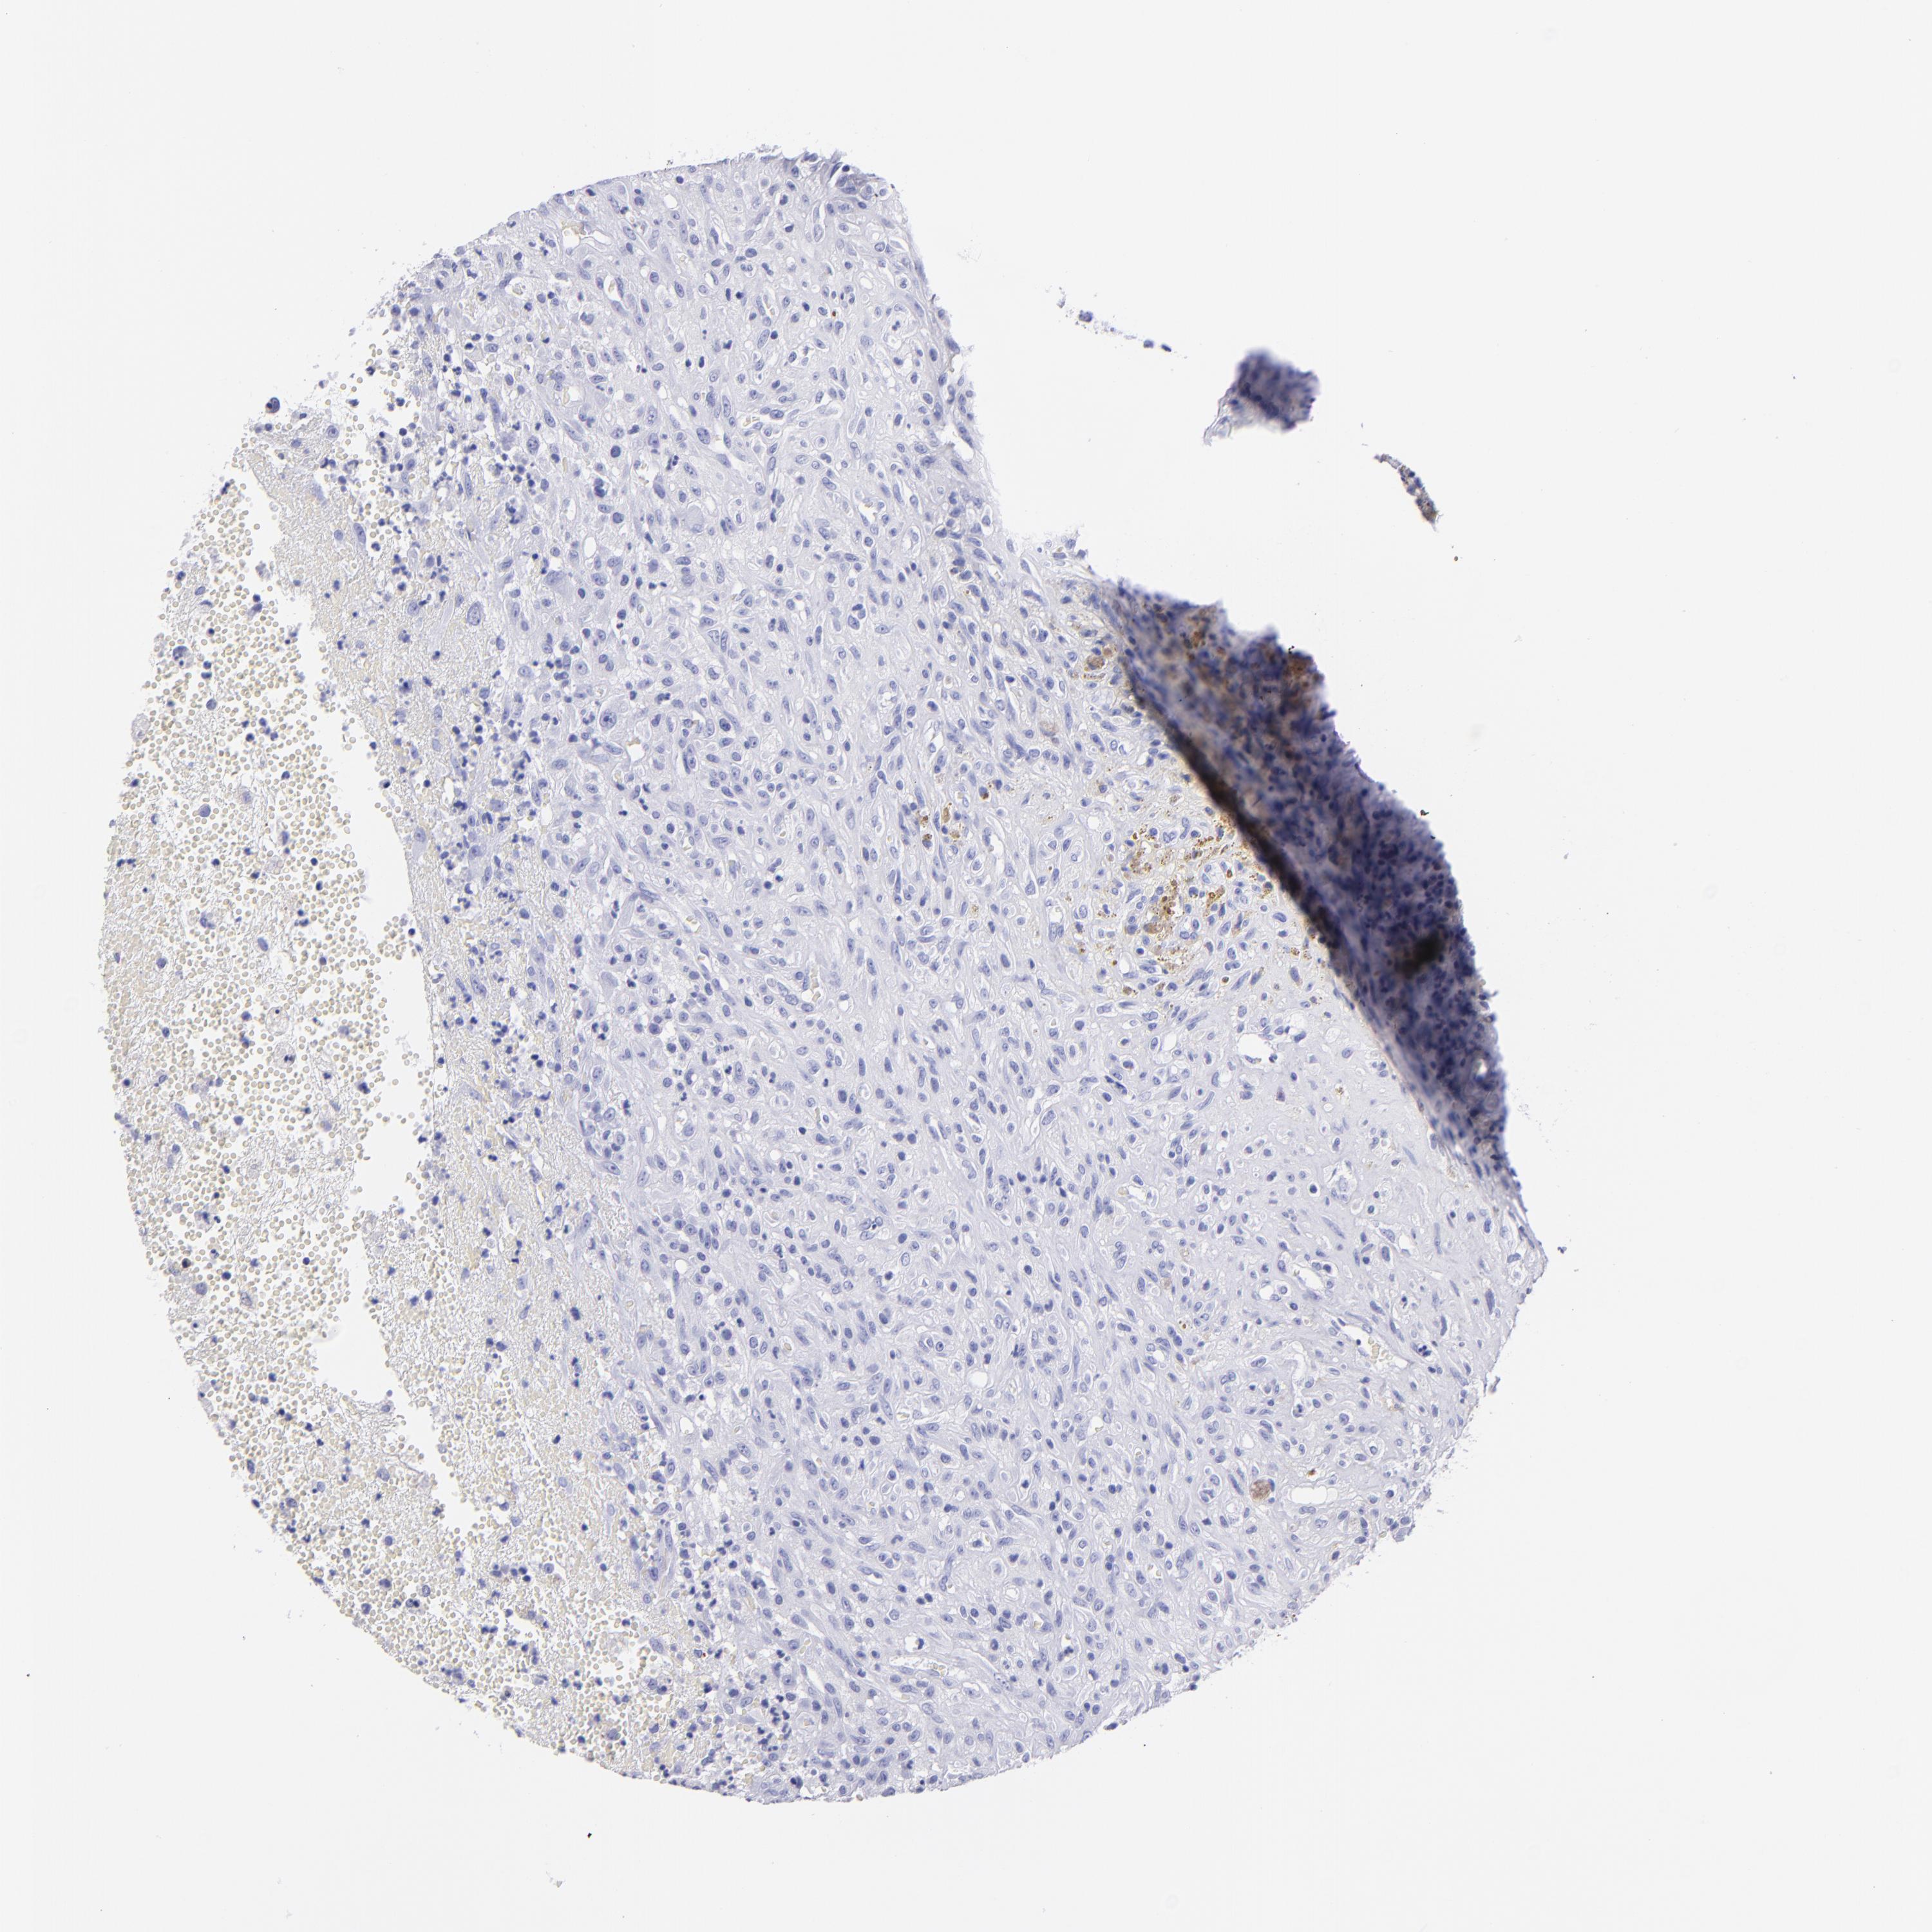

GLIOMA - Protein expressioni

A mouse-over function shows sample information and annotation data. Click on an image to view it in a full screen mode. Samples can be filtered based on level of antibody staining by selecting one or several of the following categories: high, medium, low and not detected. The assay and annotation is described here.

Note that samples used for immunohistochemistry by the Human Protein Atlas do not correspond to samples in the TCGA dataset.

Antibody stainingi

Antibody staining in the annotated cell types in the current human tissue is reported as not detected, low, medium, or high, based on conventional immunohistochemistry profiling in selected tissues. This score is based on the combination of the staining intensity and fraction of stained cells.

Each image is clickable and will lead to virtual microscopy that enables deeper exploration of all samples and also displays staining intensity scores, fraction scores and subcellular localization as well as patient and tissue information for each sample.

HPA023266

HPA023278

HPA023280

HPA023338

CAB002672

Glioma, malignant, High grade

Glioma, malignant, Low grade